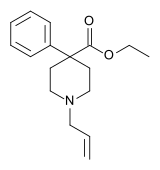

4-Phenylpiperidines

Pethidines (meperidines)

- Allylnorpethidine

Structures